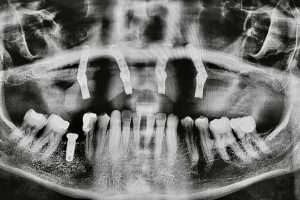

Case Study: Dental Implants & All - On - 4 /6

Before: The patient presented with severe bone loss, multiple missing teeth, and failing restorations. Daily chewing and speaking were difficult, and confidence was significantly affected.

Treatment: A full-arch rehabilitation using the All-on-4/6 dental implant technique was performed. Strategic implants were placed to maximize bone support and provide a stable foundation for a complete set of fixed teeth.

After: The patient regained full function, stability, and a natural-looking smile. The new teeth not only improved chewing ability but also restored confidence and quality of life. This transformation shows how advanced implant solutions can replace an entire arch and deliver long-lasting results.